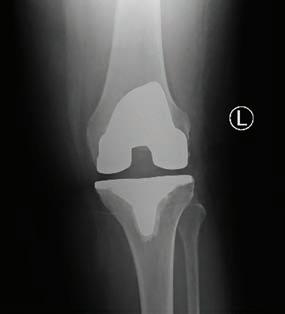

Clinical obesity is a state of excess adiposity with reduced tissue or organ function. People with clinical obesity have a chronic disease due to obesity alone. They may have various symptoms and signs directly related to obesity such as breathlessness, hip or knee pain, various metabolic abnormalities, and dysfunction related to abnormalities in other organ systems.